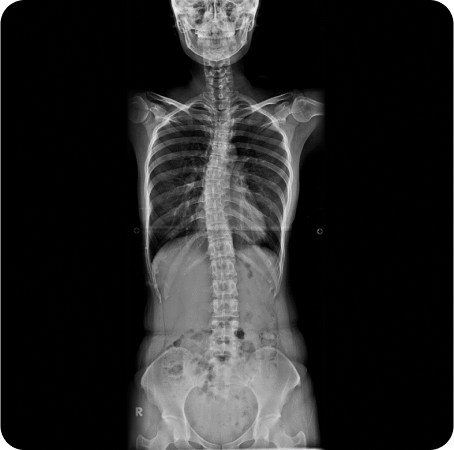

전신체형분석 X-선 검사

풀스파인 촬영으로

신체의 전체적인 문제를 파악하고

통증의 정확한 원인을 찾아

재발을 예방하고, 통증을 개선하는

치료를 합니다.

전신엑스레이 검사 등을 통한 1:1 치료 설계